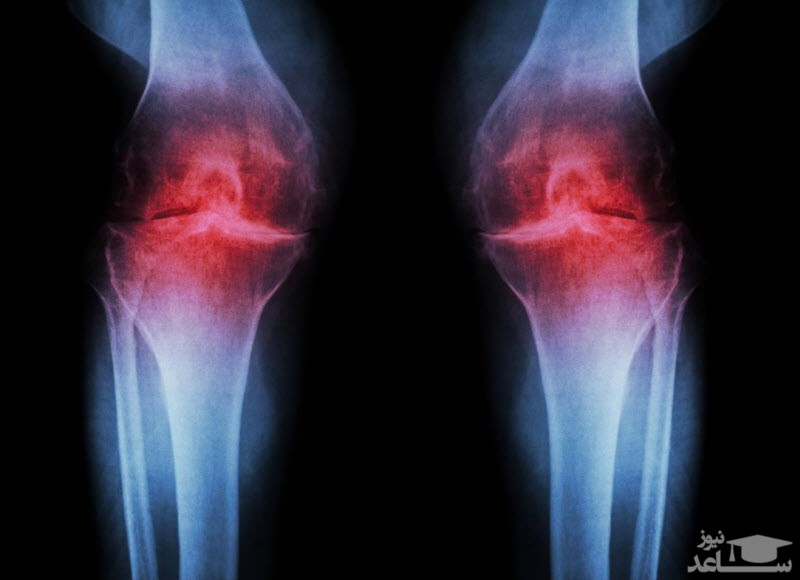

داروی نابومتون (nabumetone) از جمله داروهای کارای خانواده NSAID است. این دسته از داروها که داروهای ضد التهاب غیر استروئیدی هستند، دارای اثری مبتنی بر کاهش و بلاک کردن هورمون و موادی هستند که باعث ایجاد درد و التهاب در بدن فرد می شود. جدای از موارد فوق این دارو در کاهش نشانه های ابتلا به بیماری هایی نظیر آرتریت روماتوئید یا استئوآرتریت کاربرد ویژه ای دارد. این دارو ممکن است برای اهداف غیر از مواردی که در این راهنمای دارویی ذکر شده، استفاده شود.

اینها با هم منجر به کاهش آستانه فعال شدن می شوند و به محرک های با شدت کم امکان تولید سیگنال های درد را می دهند. شناخته شده است که PGI2 از طریق گیرنده IP متصل به Gs نقشی دارد ، هرچند که میزان سهم آن متفاوت است. پیشنهاد شده است که در شرایط التهابی دردناک مانند آرتروز از اهمیت بیشتری برخوردار باشد. با محدود کردن حساسیت ، محیطی و مرکزی ، از طریق این مسیرها NSAID ها می توانند به طور موثر درد التهابی را کاهش دهند.

PGI2 و PGE2 از طریق گیرنده های IP و EP2 به التهاب حاد کمک می کنند. شبیه به گیرنده های آدرنرژیک β، این ها متصل به Gs هستند و از طریق مسیر AC / PKA واسطه اتساع عروق می شوند. PGE2 همچنین با افزایش چسبندگی لکوسیت ها به اندوتلیوم کمک کرده و سلول ها را به محل آسیب جذب می کند. PGD2 در فعال سازی ترشح سایتوکاین از سلولهای اندوتلیال از طریق گیرنده DP1 نقش دارد. PGI2 و PGE2 فعال سازی و تمایز سلول T-helper را از طریق گیرنده های IP ، EP2 و EP4 تعدیل می کنند که اعتقاد بر این است نقش مهمی در آسیب شناسی شرایط آرتروزدارد .